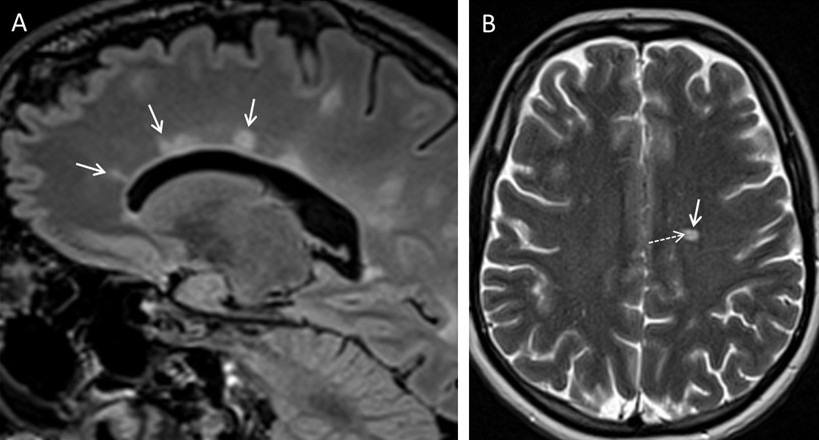

Die Diagnose einer MS stützt sich auf die Anamnese, den Nachweis neurologischer Ausfälle, die eine zentralnervöse Störung anzeigen, sowie den klinischen, kernspintomographischen oder elektrophysiologischen Nachweis einer zeitlichen und örtlichen Dissemination. Nach den international anerkannten McDonald-Kriterien (letzte Revision 2024,  Montalban et al. 2025) kann die Diagnose einer Multiple Sklerose inzwischen frühzeitig gestellt werden, wenn sich nach einem ersten Krankheitsschub im MRT Läsionen in 5 verschiedenen, für eine MS typischen Regionen finden und diese ggf. ein zentrales Venenzeichen (CVS) oder eine paramagnitschen Saum (PRL) aufweisen. Der Nachweis der bisher erforderlichen zeitlichen Dissemination durch MRT Verlaufskontrolle, also das Läsionen zu unterschiedlich Zeiten und an anderer Lokalisation im ZNS aufgetreten sein müssen muß deshalb nicht mehr zwingend erbracht werden, kann ggf. aber bei unklaren Fällen weiterhin erforderlich sein. Zudem kann durch den Nachweis MS-typischer Veränderungen im Liquor (lokale IgG-Synthese, oligoklonale Banden, kappa freie Leichtketten) die zeitliche Dissemination belegt werden.

• MRT des Kopfes und des Rückenmarkes